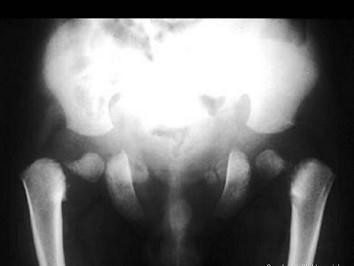

问题 男,2岁,发育迟缓,头颅软,请结合图像,选出最可能的诊断 ( )

选项 A、软骨发育不全 B、粘多糖病 C、颅锁骨发育不全 D、马方综合征 E、成骨不全

答案 C